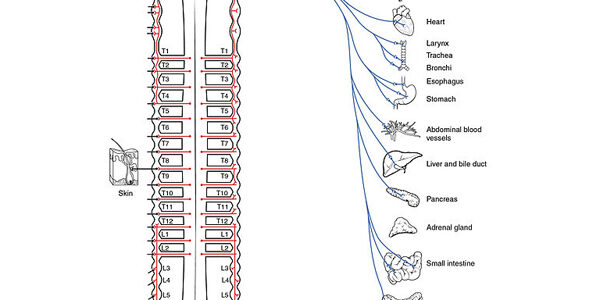

The parasympathetic nervous system, the sympathetic nervous system, and the enteric nervous system comprise the autonomic nervous system in the body. The autonomic nervous system is continuously active and is responsible for unconscious regulation of our glands and organs. The parasympathetic nervous system takes care of “rest and repair” activities, such as salivation, tears, sexual…